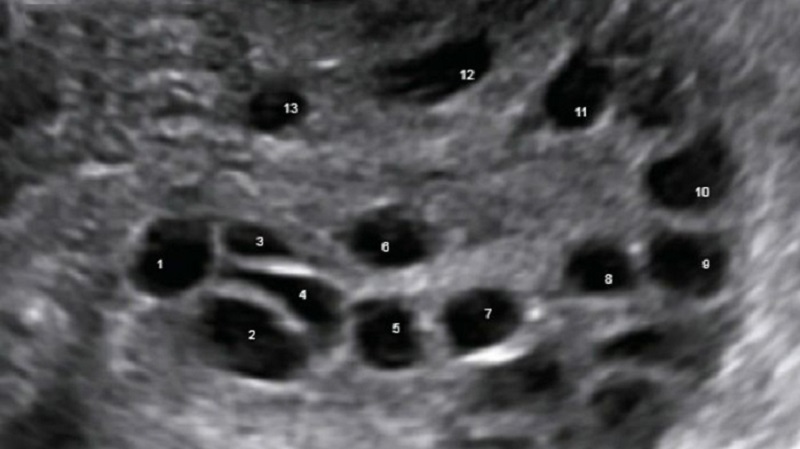

Siêu âm vùng chậu dùng sóng âm thanh tần số cao để tạo ra những hình ảnh bên trong xương chậu. Thông qua phương pháp này, bác sĩ có thể nhìn vào bàng quang, buồng trứng, cổ tử cung, tử cung và ống dẫn trứng của chị em phụ nữ.

Theo bác sĩ chuyên khoa, khi có nghi ngờ bệnh nhân bị viêm vùng chậu dựa trên những triệu chứng lâm sàng, phương pháp siêu âm vùng chậu sẽ được chỉ định để qua đó bác sĩ có thể quan sát, kiểm tra tình trạng của các cơ quan lẫn cấu trúc rắn, đồng nhất của các cơ quan nằm ở vùng chậu.

Đầu dò của máy siêu âm được đưa vào âm đạo của nữ giới để đánh giá khả năng sinh sản hoặc mang thai. Bên cạnh đó, siêu âm vùng chậu cũng được bác sĩ chỉ định trong các trường hợp khác như: Tìm dụng cụ tử cung, đánh giá sự tăng trưởng của khối u, theo dõi sự tăng trưởng của thai nhi ở phụ nữ mang thai, xác nhận thai có nằm trong tử cung hay không,... Trong một số trường hợp cần lấy mẫu sinh thiết, bác sĩ cũng có thể sử dụng phương pháp siêu âm.

Siêu âm vùng chậu là biện pháp quan trọng để bác sĩ đánh giá cấu trúc của tử cung và buồng trứng ở phụ nữ, từ đó đưa ra chẩn đoán về các vấn đề tiềm ẩn có thể gây ảnh hưởng đến sức khỏe sinh sản, bao gồm:

Phát hiện bệnh viêm vùng chậu (PID) và chẩn đoán thai ngoài tử cung là những khía cạnh quan trọng đối với sức khỏe của phụ nữ được giải quyết thông qua siêu âm vùng chậu.